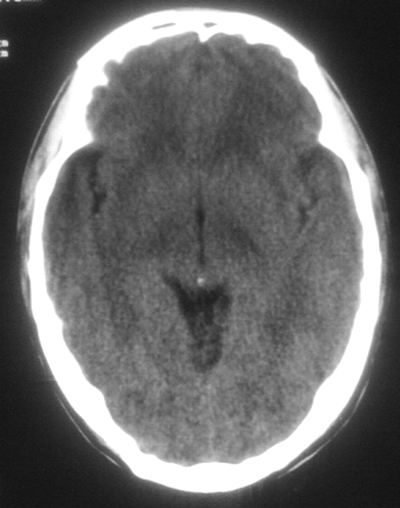

治疗三天后复查ct片示:

治疗三天后复查ct:除左侧额顶叶血肿外。左侧额叶另见片状低密度灶,密度不均匀,境界不清;考虑脑梗塞。

建议:必要时行进一步检查排除烟雾病。